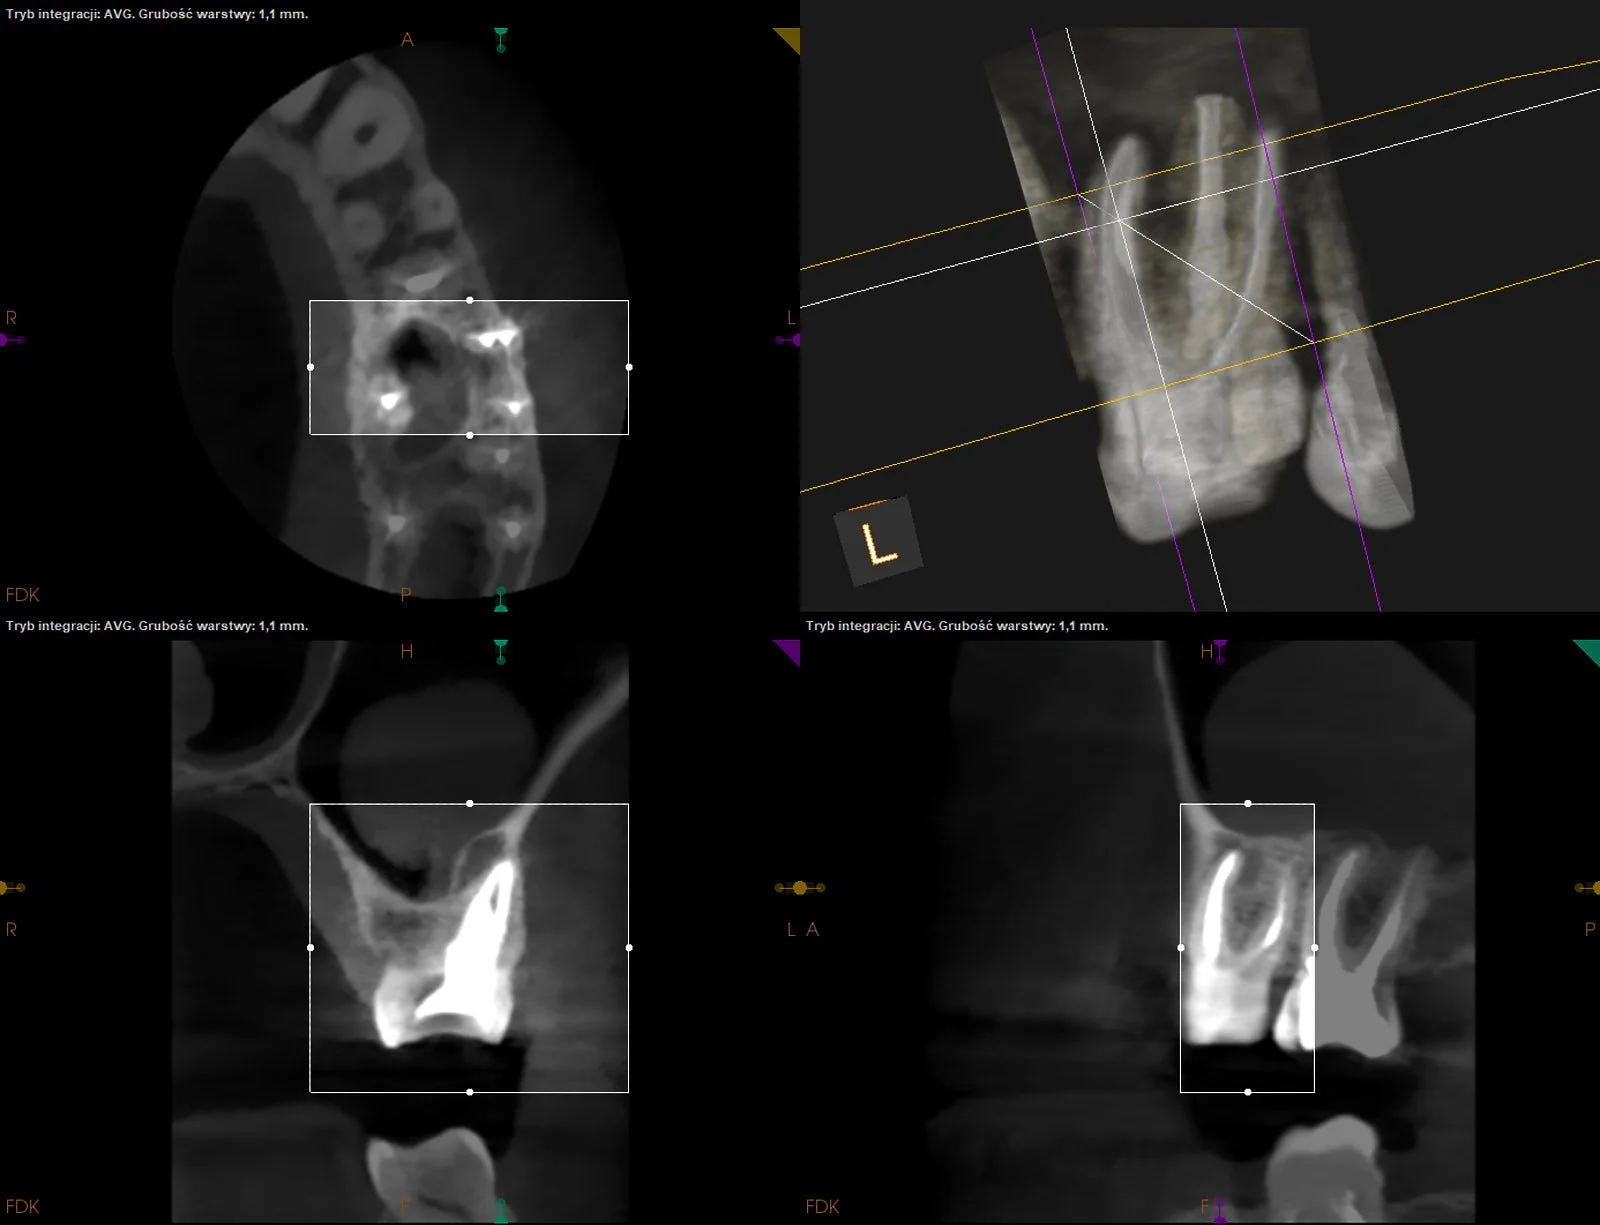

Warunkowe reendo d.21 - stan po urazie w dzieciństwie z intruzją i następową repozycją siekaczy centralnych.